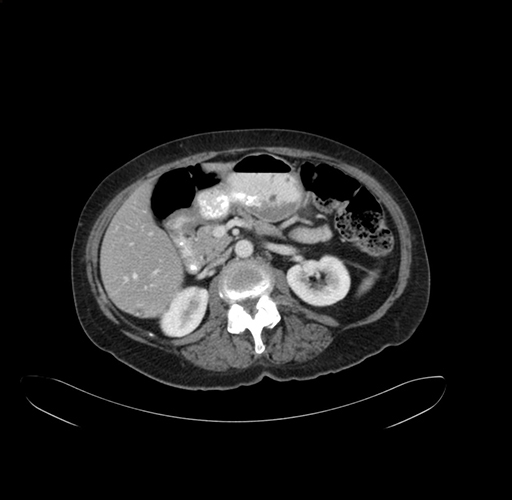

Imaging Analysis

Look through the patient's CT scan to identify any areas of concern for the necessary procedure.

Axial Venous

Based on your CT findings, which issue(s) would give reason for "planned slowing down moment(s)" in this case?

Considering a standard right hepatectomy procedure, what step(s) of the operation would you do differently in this case?